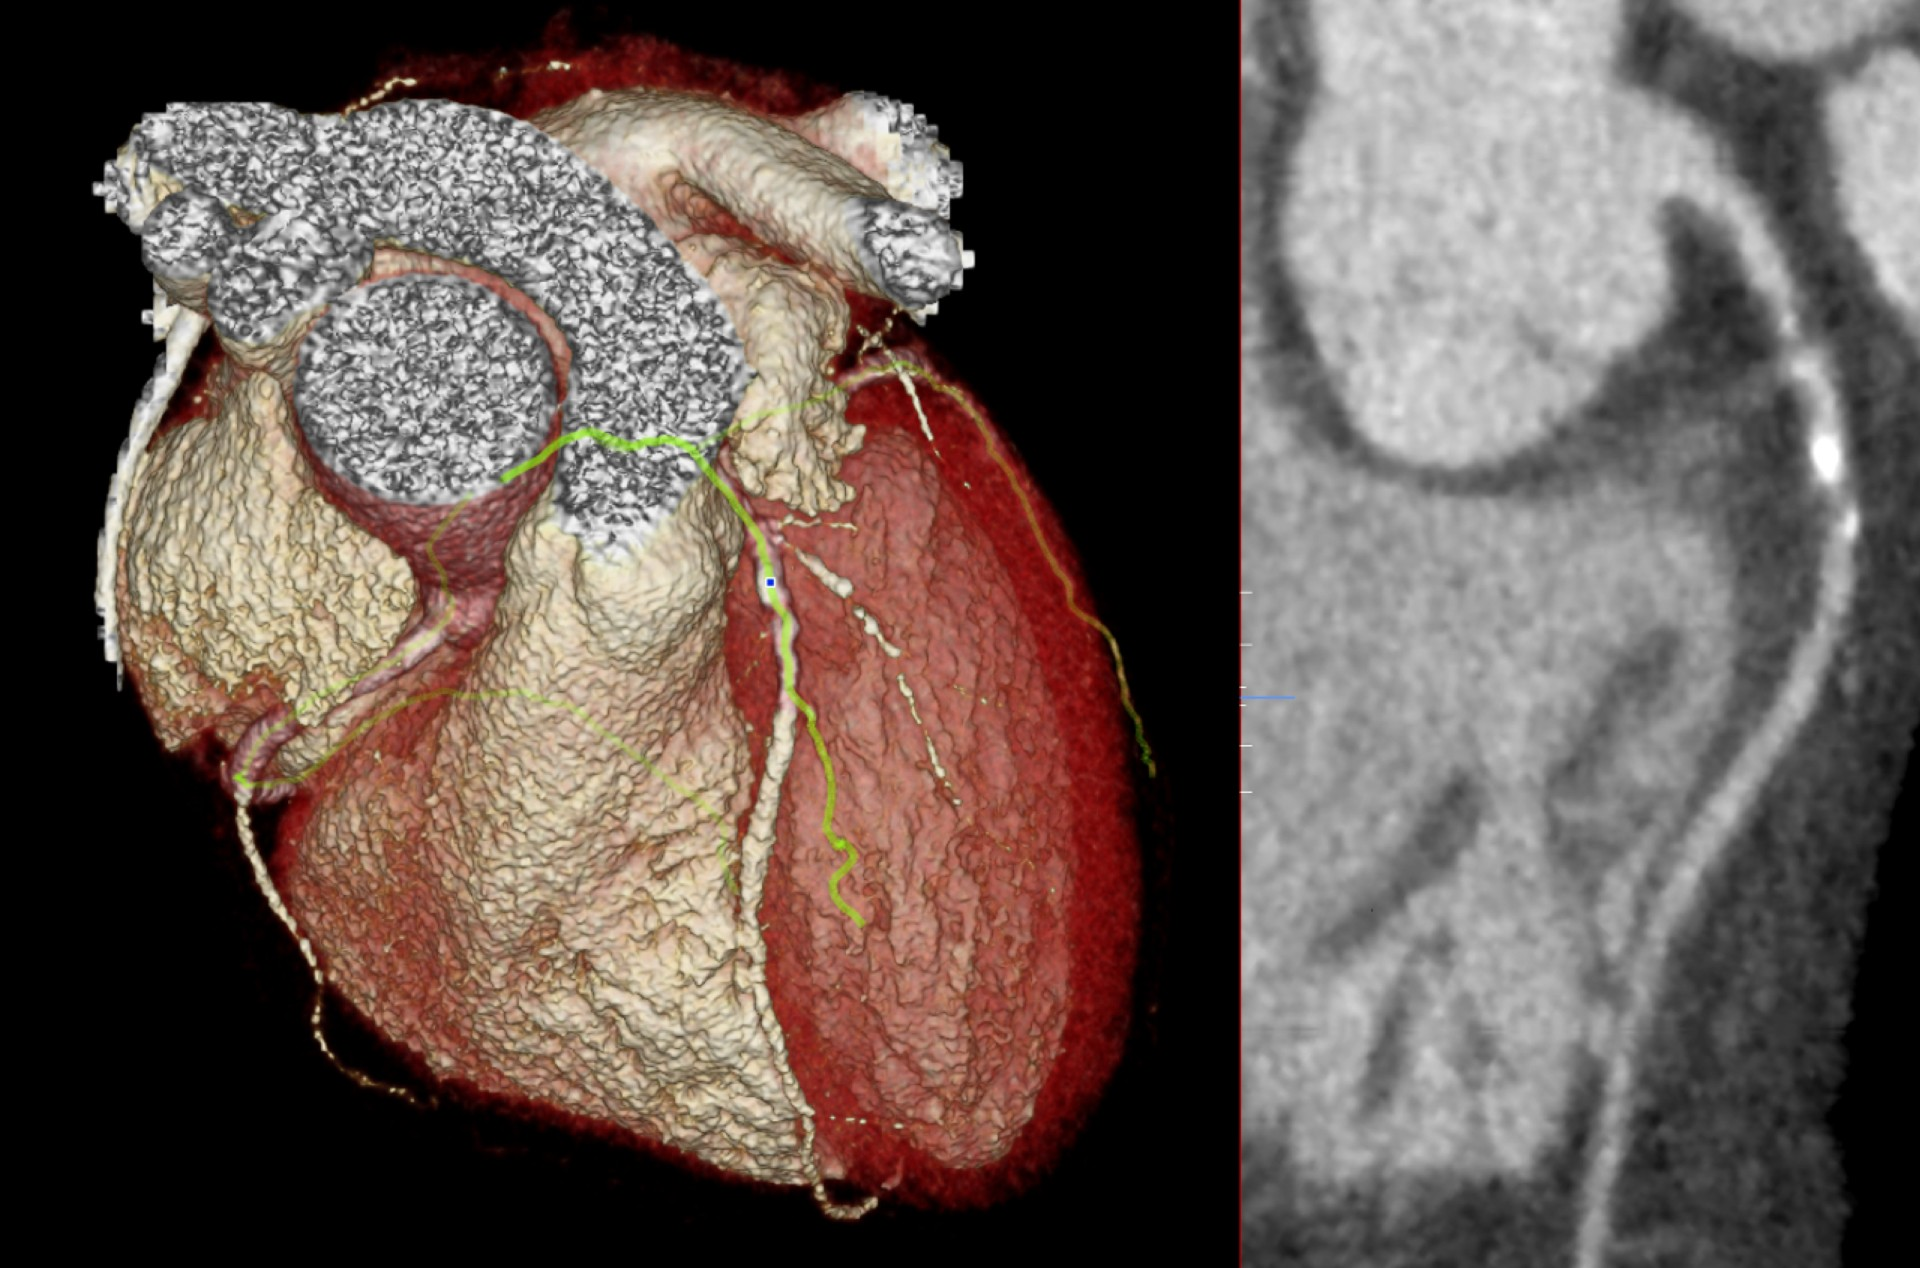

CT assessment of coronary artery disease can have a major impact on the management of patients with stable chest pain, according to new analysis from the SCOT-HEART trial presented on 1 September at ESC 2024.

CT-FFR imaging assesses adverse outcome risk in angina patients

CT angiography-derived fractional flow reserve (CT-FFR) imaging helps clinicians assess stable angina patients' adverse outcome risk -- even if they have high coronary artery calcium scores, a Danish research group has found.